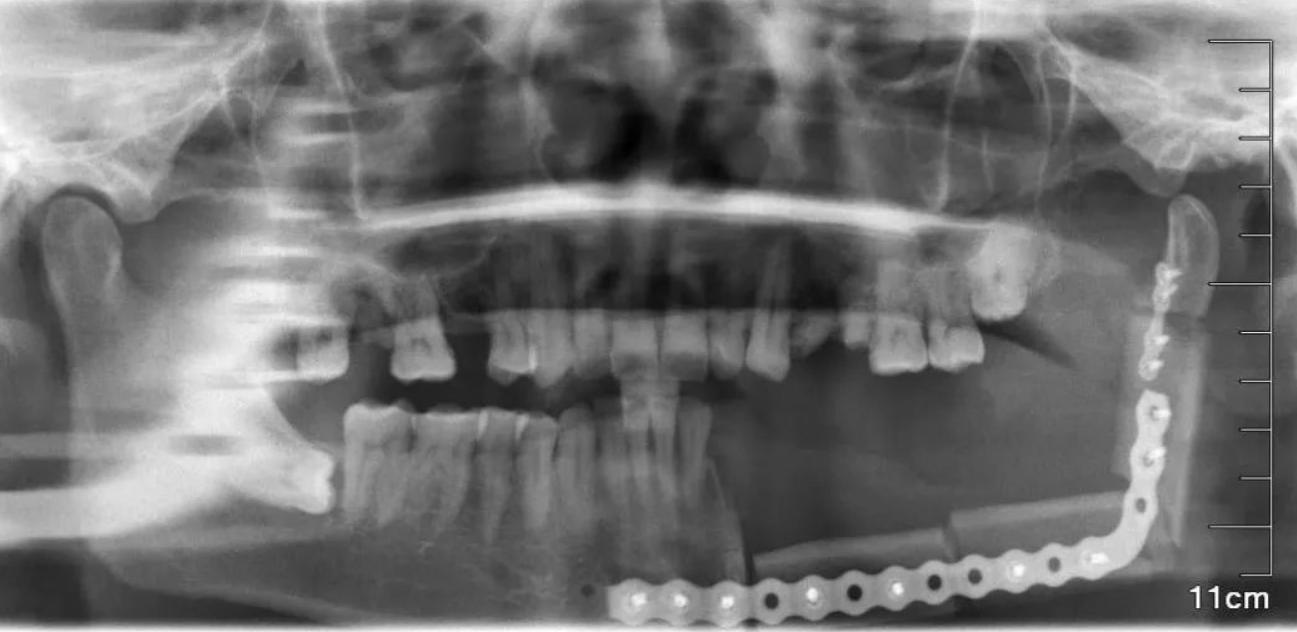

然而,除了槟榔是致癌物质之外,嚼槟榔对牙齿、口腔的危害很大,经常嚼槟榔,会严重磨损牙齿,牙齿变红、变黑,甚至提前脱落。另外长期咀嚼会加大颞下颌关节负重,从而引发脸部变形等等,所以都是威胁。曾经这样的一个说法,那就是“十个口腔癌,九个嚼槟榔”,其实这里就直接点明了槟榔对人体危害的一个事实依据,所以槟榔已经成为了威胁人类的“夺命零食”。

据相关数据显示,槟榔成品在我国的消费人口已超过6000万人,销量保持每年 20% 的增长速度,所以这是一次国人的噩梦。这里得提醒一下,嚼槟榔的朋友要多多注意,少吃可以,但是要多了确实对人类的威胁是存在的,湖南湘雅医院曾发布一则数据,在口腔颌面外科46病室,现50位住院患者有45人患口腔癌,其中44人有长期、大量咀嚼槟榔病史,可以想象下影响不是一点的小。